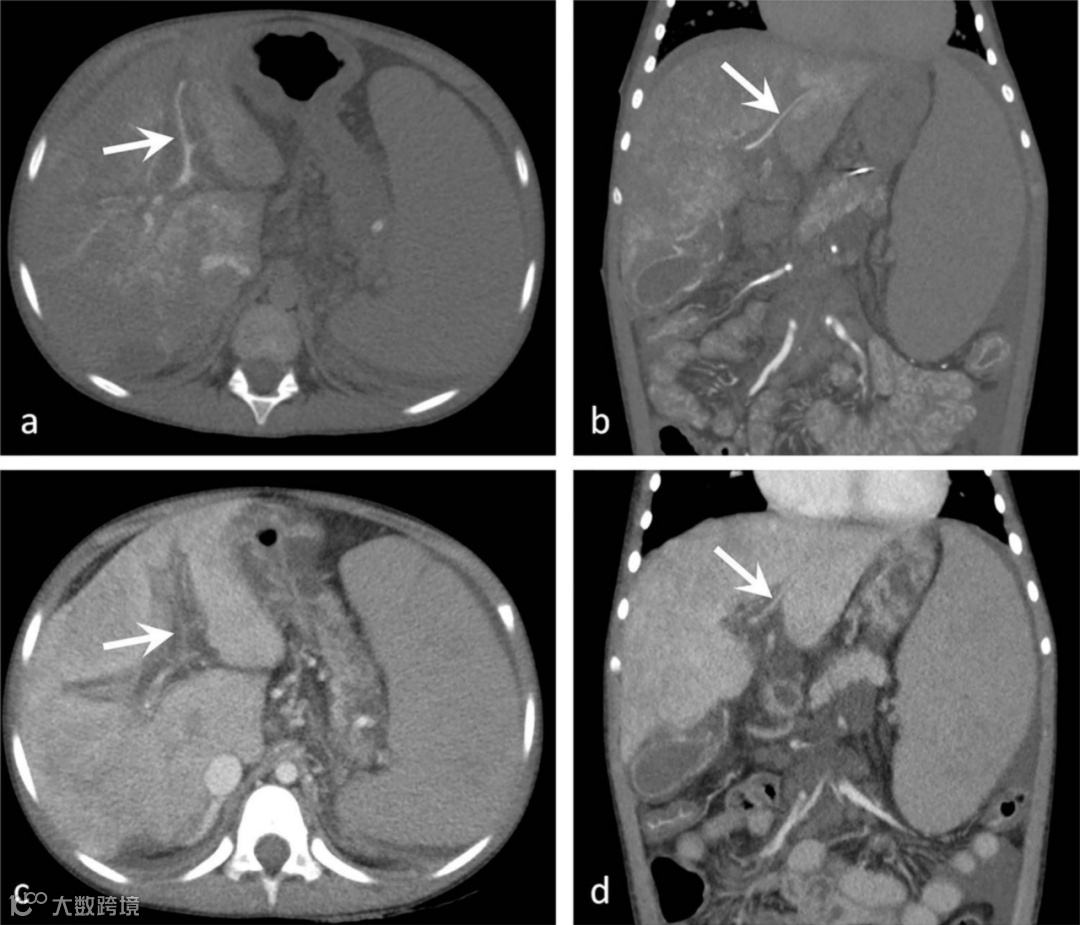

Hammer S, Zeman F, Schlitt HJ, et al. Comparison of sequential CT arterioportography-arteriosplenography with standard cross-sectional imaging and endoscopy in children with portal hypertension. Sci Rep 2022.

简评丨张金山